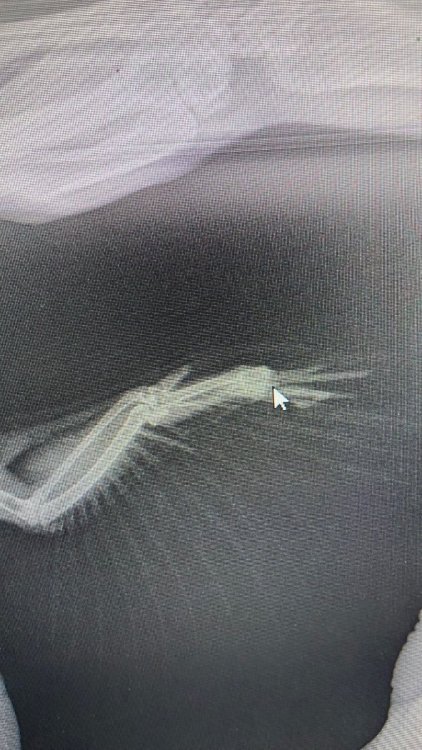

Simon.S Опубликовано 25 ноября, 2023 Автор #10 Опубликовано 25 ноября, 2023 @KatinPtic Вот фото. Действительно похоже, как-будто стержни из одного отверстия растут. И они темные, как с кровью что ли

KatinPtic Опубликовано 25 ноября, 2023 #11 Опубликовано 25 ноября, 2023 (изменено) 13 минут назад, Simon.S сказал: Действительно похоже, как-будто стержни из одного отверстия растут. И они темные, как с кровью что ли Да, очень "жестко" все..., если честно . Может хоть обезболивающее дайте ему? Ну хуже-то не будет. Если знаете какое и как давать - ну дайте, не знаете - напишите, распишу какое мнам рекомендовали, может хотя бы Ибупрофен (его как первую помощь можно для начала, а потом доктор Вам скорректирует, как сможет ответить) Смотрите, там , где Вы пальцем держите - фиксируете крыло для фото - видите как желтое что-то? Это очень похоже на гной. Но именно "похоже" - это может и свет на фото так передаваться. А вот эти волдыри - это, конечно, воспаление какое-то, видимо, перо растет - ломается, или там внутри "назревает" и одно другому мешает. Перья растущие ни в коем случае не выдергивайте, может показаться, что ему так легче будет - нет, не будет, - кровь хлынет так , что ничем не остановите, это может быть очень опасно. Такое фото Зосе отправили? Что она скажет ? Мое сообщение предыдущее видели? Про рентген? Если что - из Апрелевки лучше и ближе СББЖ на Ленинском проспекте, до Киевского вокзала доехали, тут на метро быстренько. Просто в этом СББЖ голубю точно сделают рентген, позвонить им сначала надо. Также в СББЖ на ул. Старый Гай сделают точно, но это далековато.... Изменено 25 ноября, 2023 пользователем KatinPtic

Simon.S Опубликовано 29 ноября, 2023 Автор #24 Опубликовано 29 ноября, 2023 @маленький принц Нет, не стала. Орнитолог сказал, что это может быть. У него же вся сторона деформирована. По осмотру это не фоликуллез. Перья растут криво, так как кости пальцев как-будто смяты. Да и фото сделано телефоном с компьютера, так плохо видно.